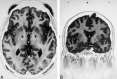

A fast spin-echo inversion-recovery (FSE-IR) sequence is described for its utility regarding surgical planning for patients with Parkinson's disease (PD) who are undergoing microelectrode-guided internal globus pallidus (GPi) ablation. Images from thirty-seven adult patients with PD were reviewed and visualization of the GPi, globus pallidus externa (GPe), and the intervening lamina was noted. High-resolution images were acquired from all patients despite the external hardware and the patients' movement disorder. In all cases, the conventional surgical trajectory, determined indirectly by a fixed measurement from the anteroposterior commissure line, was modified by the ability to visualize the GPi and optic tract directly. This sequence facilitated accurate stereotactic targeting.